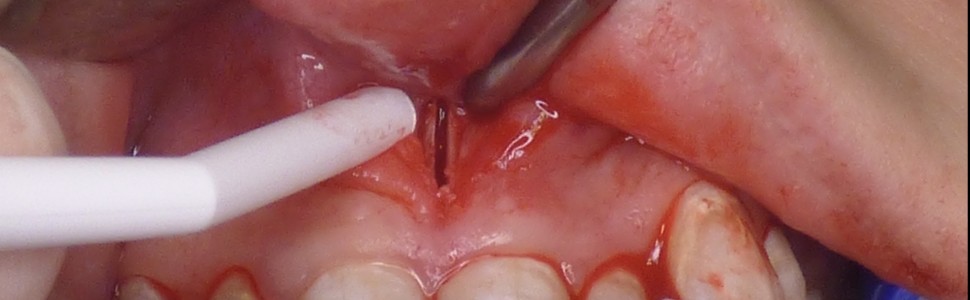

Zwężenie szczęki może mieć różnorakie podłoże, począwszy od szkieletowego, poprzez zębowe oraz spowodowane kombinacją obu wspomnianych przyczyn. Może również stanowić wadę izolowaną lub współistnieć z innymi wadami twarzowo-zgryzowymi. Zwężenia mniejszego stopnia u dorosłych mogą być korygowane bez wspomagania chirurgicznego, jednak bardziej nasilone zaburzenia koryguje się z zastosowaniem technik chirurgicznych takich jak SARME/SARPE. Szybka ekspansja podniebienia wspomagana chirurgicznie (surgically assisted rapid maxillary expansion – SARME; surgically assisted rapid palatal expansion – SARPE) stopniowo zyskuje na popularności jako opcja leczenia korygująca MTD. W pracy zaprezentowano chirurgiczny etap leczenia pacjenta, u którego został wykonany zabieg szybkiej ekspansji podniebienia wspomaganej chirurgicznie SARPE. Bezpośrednio po zabiegu został osadzony aparat typu Hyrax.

Maxillary constriction can have a variety of causes, ranging from skeletal, to dental, and caused by a combination of both. It can also be an isolated defect or coexist with other maxillofacial defects. Minor constrictions in adults can be corrected without surgical support, but more severe disorders are corrected with surgical techniques such as SARME/SARPE. Surgically assisted rapid maxillary expansion/surgically assisted rapid palatal expansion (SARME/SARPE) is gradually gaining popularity as a treatment option to correct maxillary transverse deficiency (MTD). The study presents the surgical stage of treatment for a patient who underwent surgically assisted rapid palatal expansion (SARPE). A Hyrax appliance was placed immediately after the treatment.